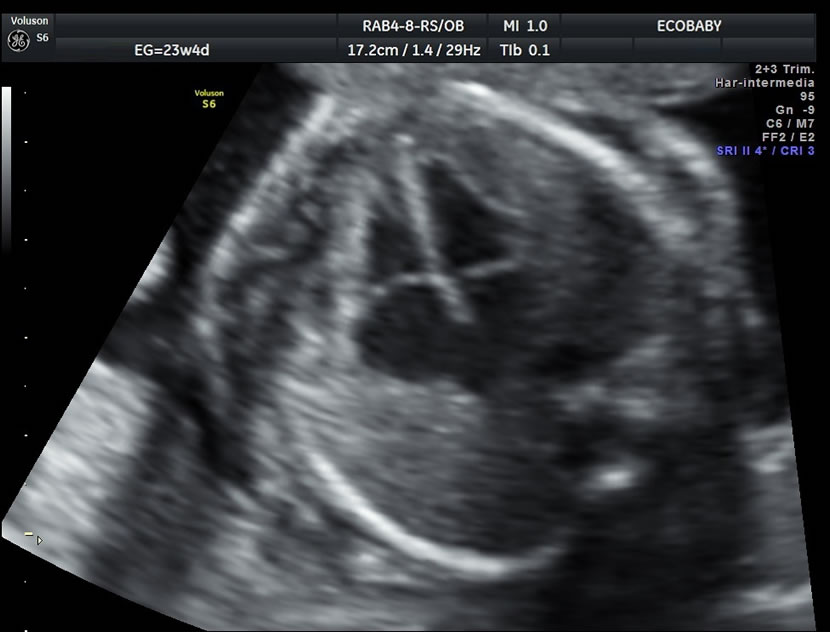

Cerebro, cuello, cara, tórax, corazón (diferentes cortes que muestran las cavidades y la correcta entrada y salida de arterias y venas), abdomen (normalidad de la pared, estómago, intestino, riñones, vejiga), miembros inferiores y superiores y columna vertebral.